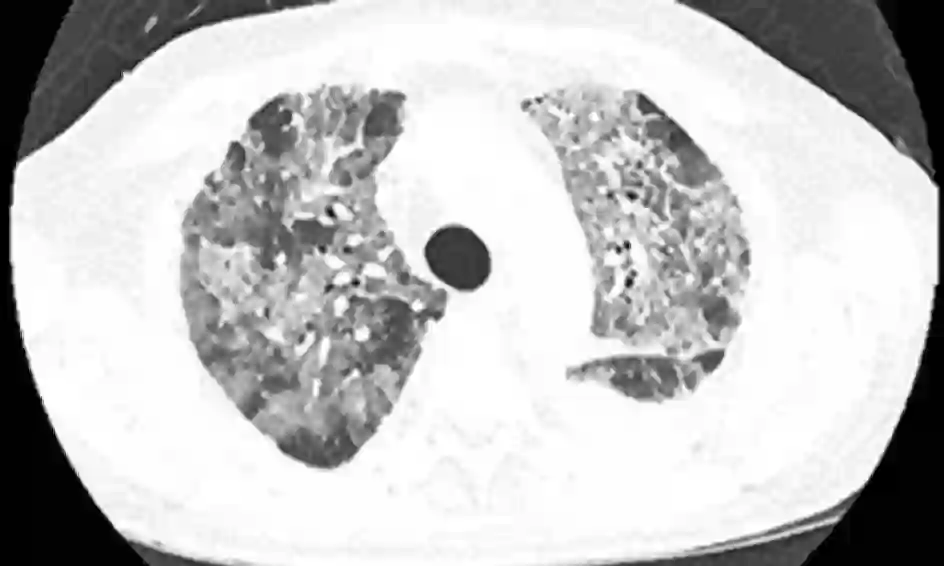

患者是一名54岁的老年男性,被确诊为肺大细胞神经内分泌癌,并且已经出现了转移。最初,病人使用了卡铂和紫杉醇进行治疗,随后又使用了顺铂和依托泊苷,同时接受了定向放疗。但是传统治疗的疗效并不理想,病人很快出现了中枢神经系统和肝脏的转移,因此帕博利珠单抗每3周2mg/kg的治疗方案再次临危上阵。在治疗5个疗程后,病人开始出现呼吸困难和咳嗽(无发热),氧饱和度仅为84%,CT检查显示其双肺出现了磨玻璃样变性。因此,病人开始每6小时使用哌拉西林-他唑巴坦4.5g的甲羟泼尼松2mg/kg进行治疗,在治疗开始后的24小时内,病人的肺部病情就出现了好转,治疗1周后的CT检查显示,病人肺部原先的浑浊阴影几乎全部消失。